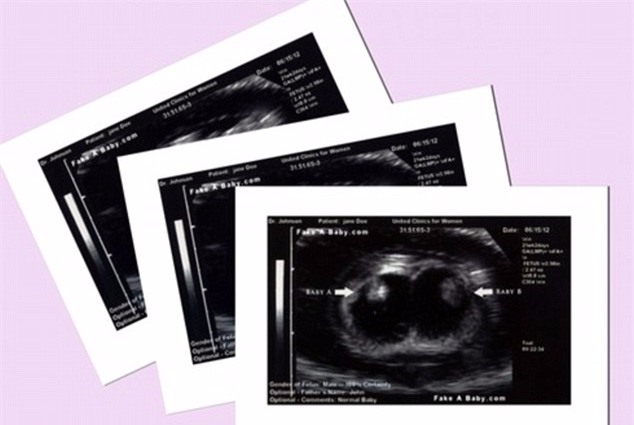

Cùng lúc ấy, một thành viên của nhóm “Moms of Triplets” phát hiện điều bất thường trong hình ảnh siêu âm cô gái đã đăng trên mạng nên đã liên lạc với gia đình. Hóa ra tất cả những ảnh siêu âm đều là giả, ngay cả cái bụng bầu cũng là đồ giả và được cô gái tìm mua trên trang mạng chuyên bán các loại phụ kiện giả bụng bầu.

“Hình siêu âm của 3 đứa bé giống hệt hình chúng tôi thấy trên mạng”, Tracy Matthews, một người bà con của Jordan lên tiếng.

Trang web bán đủ mọi phụ kiện để giả mang thai, từ bụng bầu đến hình siêu âm.